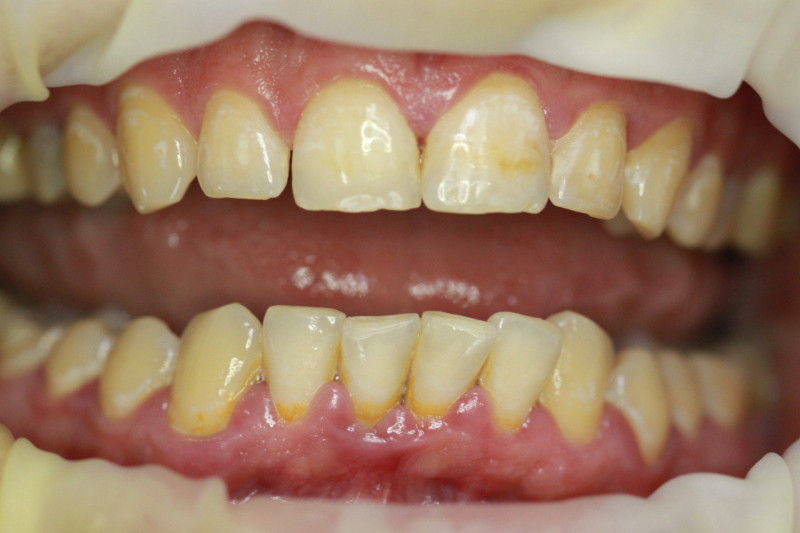

Index Dual — это диагностический маркер, предназначенный для идентификации зрелости зубных отложений. В современной стоматологии это «детектор лжи» для пациента и навигационная карта для врача. Без использования подобных средств эффективность профессиональной чистки снижается, поскольку до 30% налёта остаётся незамеченным в межзубных промежутках и поддесневой зоне.

Index Dual работает по принципу селективного окрашивания: свежий налёт (до 24 часов) становится розовым, а зрелый кариесогенный налёт (более 24 часов) — синим.

Высокая контрастность Хорошо видно даже в пришейной зоне